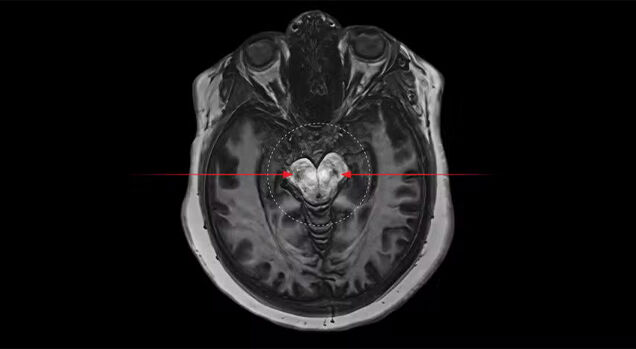

O canabidiol, conhecido pela sigla CBD, é um dos principais compostos estudados da cannabis medicinal. Pesquisas clínicas e revisões sistemáticas comprovaram sua eficácia em casos de depressão, epilepsia refratária, dor crônica e distúrbios neurológicos. O mecanismo de ação do CBD envolve a modulação do sistema endocanabinoide, importante na regulação das funções neurológicas, imunológicas e metabólicas.